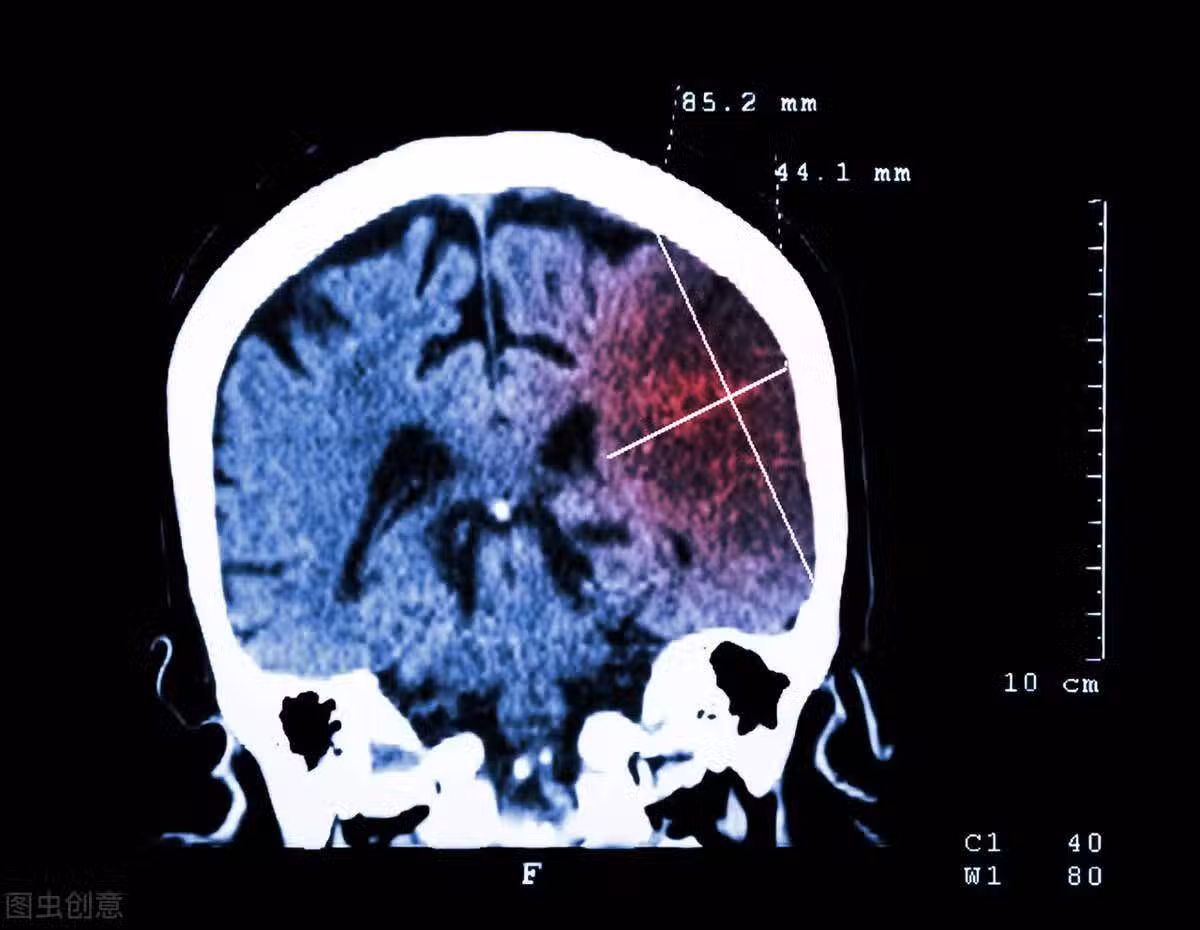

吃什麼能預防腦梗?研究發現:1類食物能降低風險,50歲以上必看!

英國國家醫療服務體系(NHS)指出, 食用足夠量的膳食纖維可以降低患心臟病、中風、2型糖尿病和腸癌的風險。